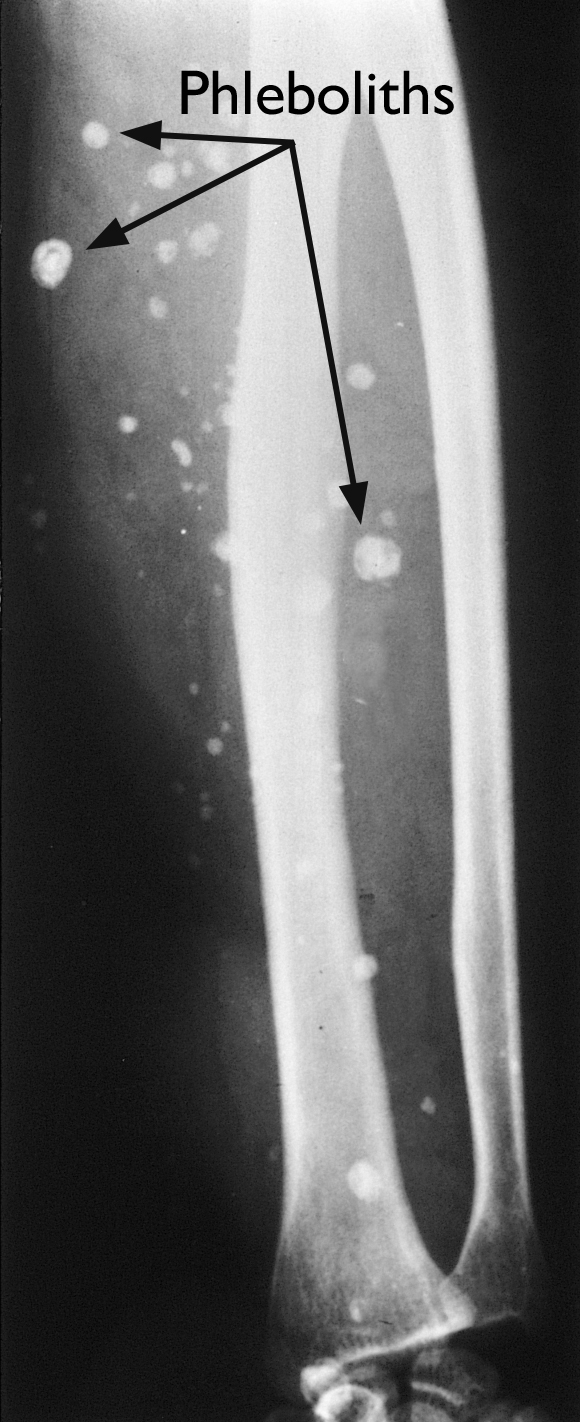

What Are Vascular Phleboliths . Phleboliths are calcified thrombi found in veins, venulae, or the sinusoidal vessels of hemangiomas (especially the cavernous type). A phlebolith is a small, round calcification that can form in blood vessels. They are particularly common in the pelvis, where they may mimic ureteric. However, some cases might happen from conditions such as venous. A phlebolith is a small local, usually rounded, calcification within a vein. Phleboliths are tiny calcifications (masses of calcium) located within a vein. They are sometimes called “vein stones.” the phlebolith starts. Phleboliths are literally vein stones, and represent calcification within venous structures. These layers of calcium and fibrous tissue coat old. Phleboliths are calcium deposits that build up in the veins. These are very common in the veins of the lower part of the. Most often, the cause isn’t known.